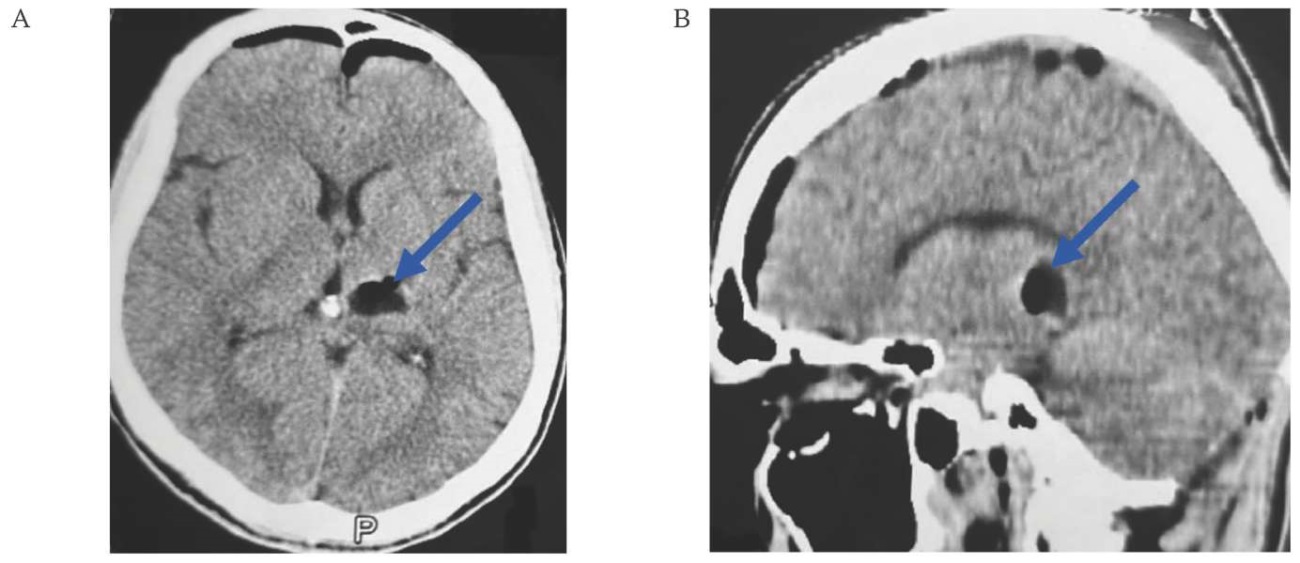

A control CT scan in the postoperative period was performed on the third day; according to the study data, the condition after median suboccipital craniotomy, residual cavernoma, and repeated hemorrhage were not detected (Fig. 4A, B).

FIG. 4. Computed tomography of a 38-year-old patient on the 4th day after removal of a cavernous malformation in the dorsal part of the left peduncle of the midbrain (June 01, 2024).

A. Axial section: the cavernoma with the hematoma capsule is completely resected (arrow).

B. Sagittal section: the cavernoma with the hematoma capsule is completely resected (arrow).